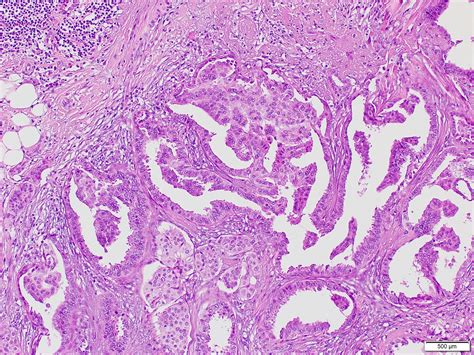

Pathology outlines are comprehensive documents that detail the microscopic characteristics of the breast cancer tissue. These outlines are prepared by pathologists, who are like detectives of the medical world, examining tissue samples under a microscope to identify and describe abnormalities. The pathology outline includes crucial information such as the type of cancer (e.g., invasive ductal carcinoma, invasive lobular carcinoma), the grade of the cancer (how abnormal the cells look), the size of the tumor, and whether the cancer has spread to nearby lymph nodes. It also includes the results of special tests, like immunohistochemistry, which determines the ER, PR (progesterone receptor), and HER2 status of the cancer cells. All this information is essential for staging the cancer and planning treatment.